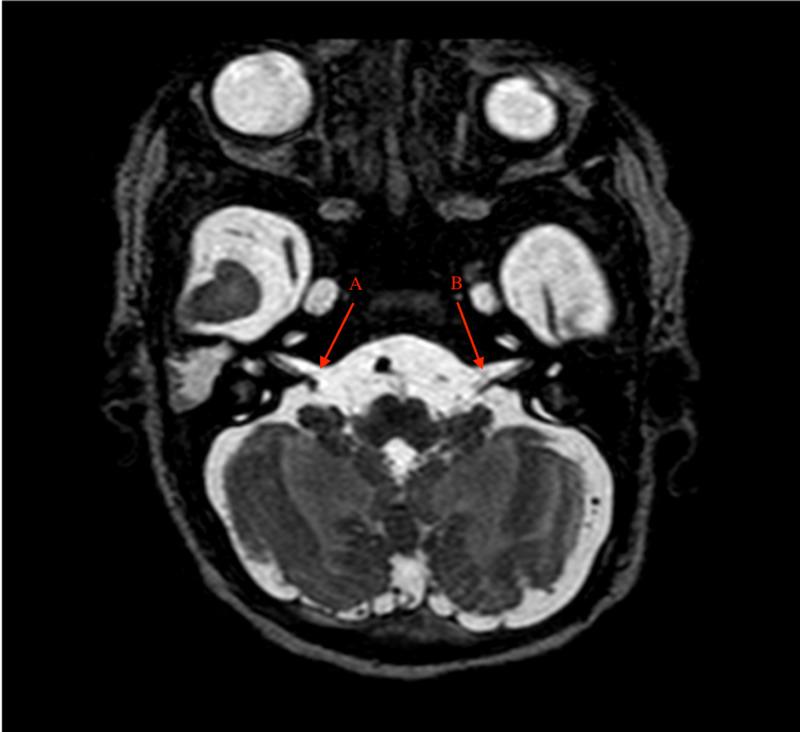

Poland-Mobius syndrome is a rare congenital disorder that includes features of Poland and Mobius syndromes. It is characterized by unilateral or bilateral congenital facial weakness, impairment of abduction of eyes, associated limb anomalies, and aplasia or hypoplasia of the pectoralis muscle. We describe a case of Poland-Mobius syndrome in a neonate associated with unilateral vocal cord immobility.

波兰-莫比乌斯综合征是一种罕见的先天性疾病,包括波兰综合征和莫比乌斯综合征的特征。其特点是单侧或双侧先天性面部无力、眼球外展障碍、相关肢体异常以及胸肌发育不全或发育不良。我们描述了一例新生儿波兰-莫比乌斯综合征合并单侧声带麻痹的病例。